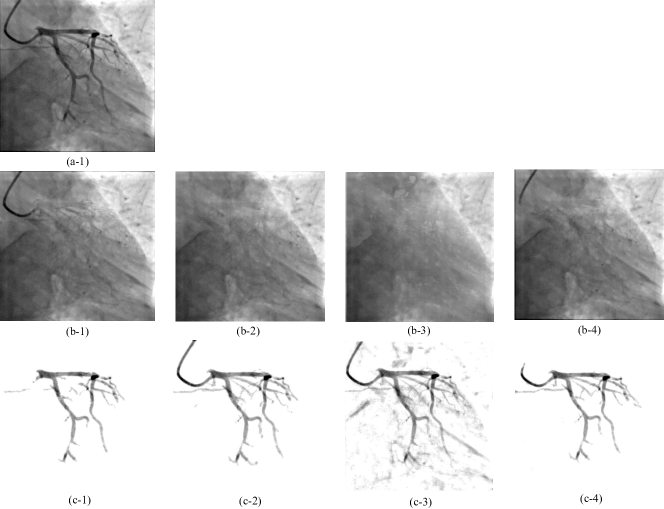

Refer to caption

Figure 4: Two instances of feature visualizations for illustrating the CAB’s effects: suppresses the noises in the background areas while highlights the foreground vessel feature. From left to right, each row displays the original XCA image; the 2nd channel of fused spatial feature maps in the output of the second skip connection layer (Fig. 1) before inputting to the CAB, it contains noise pollution from the background areas; the 2nd channel of refined feature maps from the output of CAB in the decoder stage (Fig. 1). The background noise is reduced and the foreground vessel feature is highlighted via the channel attention operation.

Through the operation of CAB, the SVS-net can adaptively highlight some channel information meanwhile suppress the trivial channel information. Hence, the predicted probability map is gradually improved. Inspired by the works [58, 63], we introduce the CAB to weight the feature maps from the low-stage output from the skip connection layer and then combine with the corresponding high-stage feature maps that are outputted from the upsampling layer. High-stage output feature maps contain more advanced global semantic information while low-stage feature maps contain more detailed yet noisy information, therefore the high-stage features can provide clues to screen useful information from low-stage feature maps and generate more pure feature representation. Under the guidance of high-stage features, the attention weights are learned and used to obtain discriminative salient features. As shown in Fig. 4(a3)(b3), the low-stage feature map from the output of skip connection layer is refined by the CAB. From the Fig. 4(a2)-(a3) and Fig. 4(b2)-(b3), the background noises in Fig. 4(a2)(b2) are greatly reduced while the foreground vessel features are highlighted in Fig. 4(a3)(b3).